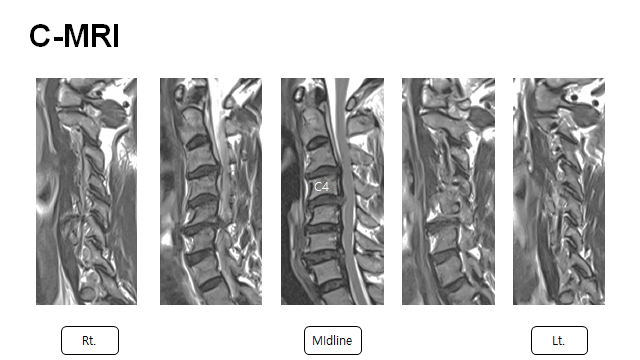

MR 상에서 보이는 cord signal change

HCD C3/4 4/5 c OPLL C4 with cord compression

ACDF C3/4/5 + VBSO(vertebral body sliding osteotomy) C4